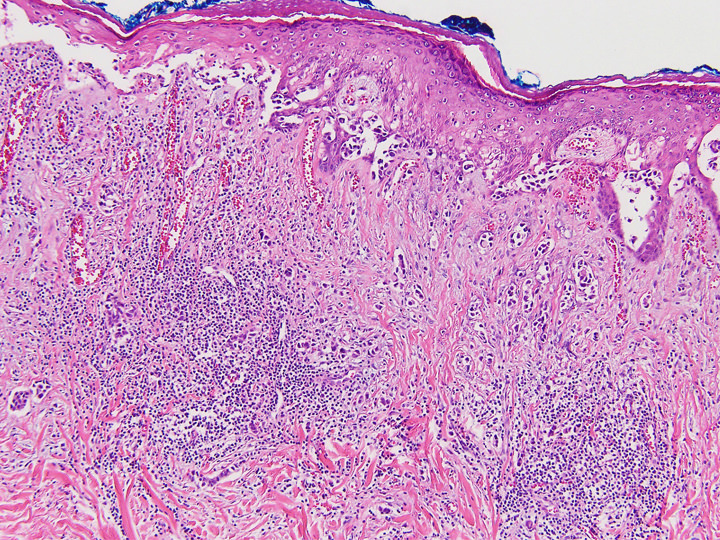

Microscopic (histologic) description

- Single cells or clusters of cells spread throughout the epidermis

- Cells have abundant pale cytoplasm, large irregular nuclei with prominent nucleoli

- Underlying dermis may have chronic inflammation

- Epidermis with hyperkeratosis and possibly ulceration

- Florid cases can show gland formation

- Paget cells may phagocytose melanin, mimicking melanocytes

- Underlying carcinoma is most commonly high grade invasive carcinoma of no special type (NST; 53 - 64%) or DCIS (24 - 43%) (Histopathology 2020;77:181)

Microscopic (histologic) images

Contributed by Anna Biernacka, M.D., Ph.D. and Mary Ann Gimenez Sanders, M.D, Ph.D.